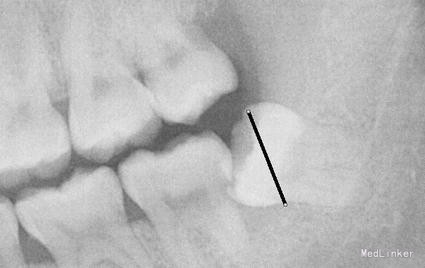

检查: 18.28颌面龋坏,质地软,牙颈部脱矿,叩诊(-),不松动。 37玻璃充填物,叩诊(-),不松动,冷热刺激正常。 38近中水平阻生,牙龈无红肿,叩诊(-),探诊有盲袋,盲袋内食物碎屑。 47缺失多年,48近中向移位,间隙1mm,叩诊(-),不松动。

治疗计划:18、28,38拔除。 37重新充填。 48观察。 治疗:28局麻下拔除。 38阻滞下拔除。

拔牙常用牙挺的三步骤、 第一步、楔法:置挺时,插入牙根与牙槽骨之间,然后施力,边旋动,边楔入,使牙在牙槽窝内逐渐松动 ↓ 第二步、推法:将挺刃插在所拔牙牙齿的近中面或颊侧面与牙槽骨之间,使挺刃的凹面朝向根面凸面支靠在颊侧近中牙槽嵴上作为支点。用靠近冠部的挺刃推动所拔牙,使该牙受力后被推向远中或者舌侧而松动,但不包含使牙脱出牙槽的力。 其实说白了推法楔法差不多,只是用力方向幅度大小不同。 楔是向下楔入,推是增大间隙。 第三步、挺法:置放方法与推法一致,只是用力方向变了。向远中面方向旋动牙挺时,使紧贴颈部根面的挺刃向所患牙使力,使其受力后被挺向远中并向合面方向移动。再逐渐加大牙挺旋动的幅度,并将挺刃逐渐向牙槽内插入(配合楔法),牙的松动度也随之增大。最后,使该牙将向合面与远中的合力方向松动脱位。